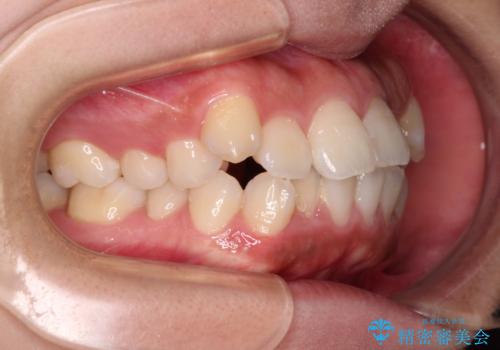

くちばしのような前歯が気になる ワイヤー装置による抜歯矯正治療

- 前歯の出っ歯と口元の閉じにくさを気にして来院された患者様です。

口元を積極的に引っ込めるために、上下左右の小臼歯4本を抜歯することとしました。